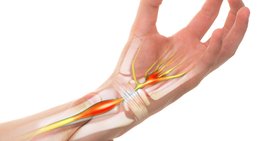

Karpaltunnelsyndrom

Das Karpaltunnelsyndrom ist ein Nervenengpasssyndrom und eine häufige Erkrankung im Bereich der Hand. Es entsteht in Folge einer Enge des Karpaltunnels und...